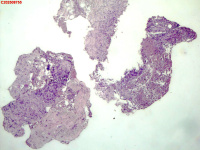

| 图片: | |

- 右侧胸壁穿刺组织活检

| 性别 | 女 | 年龄 | 81岁 | 临床诊断 | 胸锁关节结核? |

| 一般病史 | 胸部CT示:右肺下叶小结节,建议3-6个月复查,必要时胸外科会诊。左肺上叶多发小斑点、结节影,结核可能。右肺上叶多发点状影。双肺间质性改变。纵隔淋巴结肿大、钙化。右侧胸锁关节见骨质破坏,周围见软组织肿胀。 | ||||

| 标本名称 | 右侧胸壁穿刺组织活检 | ||||

| 大体所见 | B超:体表包块彩超示右侧胸壁混合回声包块,右侧胸壁低回声区,CDFI示:其内未见明显血流信号。 | ||||